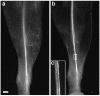

A direct histological assay of axonal regeneration would have many advantages over currently available behavioral, electrophysiological, and radiometric assays. We show that peripheral sensory axons marked with the yellow fluorescent protein in transgenic mice can be viewed transcutaneously in superficial nerves. Degenerating and regenerating axons can be followed in live animals with a dissecting microscope and then, after fixation, studied at high resolution by confocal microscopy. Using this approach, we document differences in regenerative ability after nerve transection, crush injury, and crush injury after a previous "conditioning" lesion. We also show that the chemotherapeutic drug vincristine rapidly but transiently blocks regeneration and that the immunosuppressive drug FK506 modestly enhances regeneration. Moreover, FK506 nearly restores normal regenerative ability in animals treated with submaximal doses of vincristine. Because neuropathy is the major dose-limiting side effect of vincristine, we propose that its efficacy could be enhanced by coadministration of FK506 analogs that are neuroactive but not immunosuppressive.